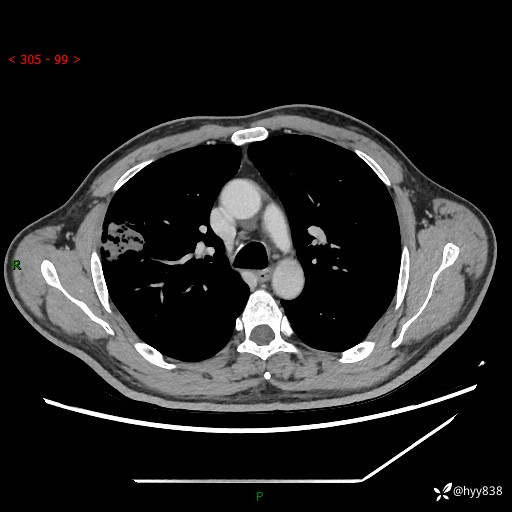

现病史:患者2天前体检完善胸部CT提示:右上肺团块影,炎症可能,肿瘤性病变不除外,冠状动脉钙化,无咳嗽、咳痰,无寒战发热,无恶心、呕吐等其他特殊不适,未予以特殊治疗,现为明确病变性质来我院就诊,门诊以“肺肿物性质待查”收入我科。 起病以来,患者精神、饮食、睡眠可,大小便正常,体力体重较前无明显变化。

胸部CT平扫+增强